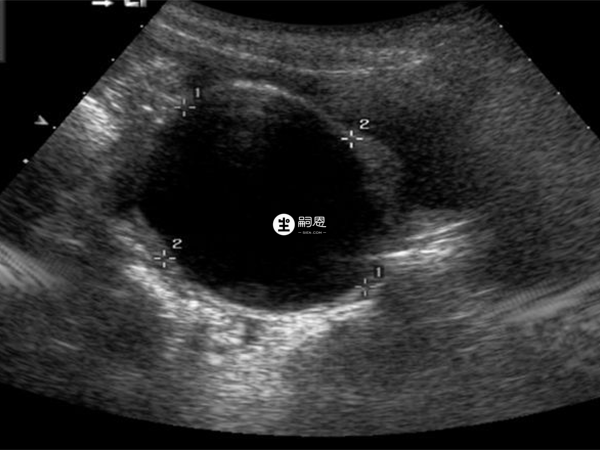

巧克力囊肿也叫卵巢子宫内膜异位囊肿,它是子宫内膜在卵巢内生长而形成的一种囊肿,因为囊肿内部有陈旧性积血呈褐色,其形态是黏稠如液态巧克力,所以被称为巧克力囊肿,该疾病虽然是良性病变,但如果巧克力囊肿10年了一直没治疗可能会导致以下后果: